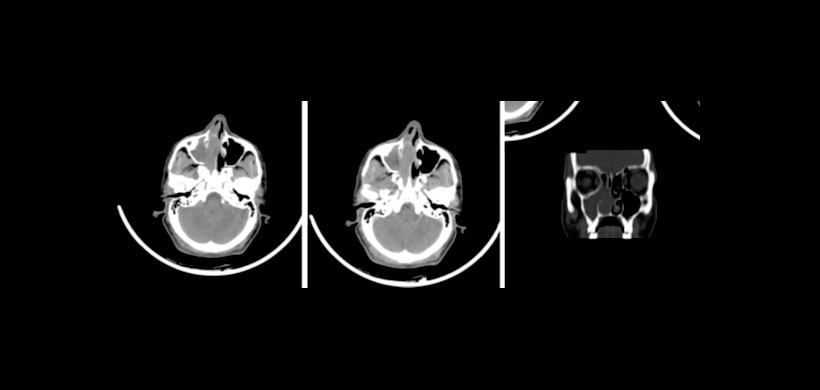

En cuanto a investigación la CT es el gold standar para la descripción de la enfermedad inflamatoria del seno ocasionada por una obstrucción. También las imágenes de cortes coronales están estrechamente correlacionada con el abordaje quirúrgico.

Por lo tanto, la TC es el estudio preferido para la cirugía endoscópica funcional del seno (FESS) porque las imágenes coronales imitan la apariencia de la cavidad sinonasal desde la perspectiva del endoscopio.